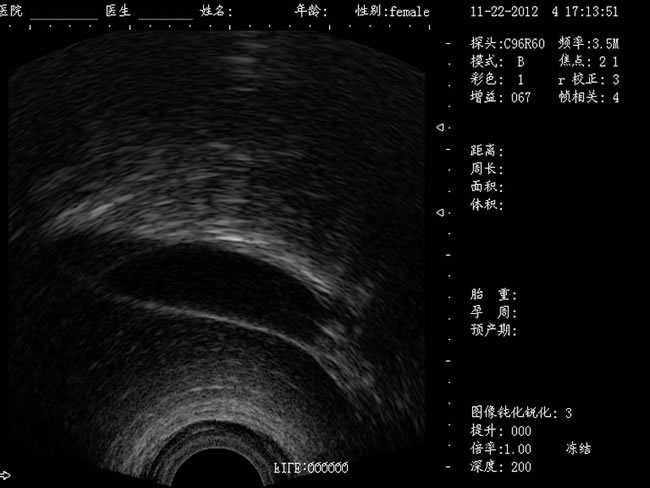

定位精確 手術(shù)效率高:實(shí)時(shí)動(dòng)態(tài)頻率掃描等全數(shù)字超聲成像技術(shù)、生成精確的圖像引導(dǎo)手術(shù)器械迅速到大手術(shù)位置,避免損傷子宮內(nèi)膜和子宮穿孔的現(xiàn)象,即減輕了患者的痛苦又極大提高了手術(shù)效率。

高密度全數(shù)字波束形成:采用全新一代混頻技術(shù)、數(shù)字嵌入系統(tǒng)及數(shù)字整序技術(shù)

有效提升系統(tǒng)的穩(wěn)定性、可靠性:實(shí)時(shí)動(dòng)態(tài)孔徑成像,充分保證圖像的精度和清晰度

CXA10R/6.5MHz 腔內(nèi)探頭

選配:CXA60R/3.5MHz 凸陣探頭